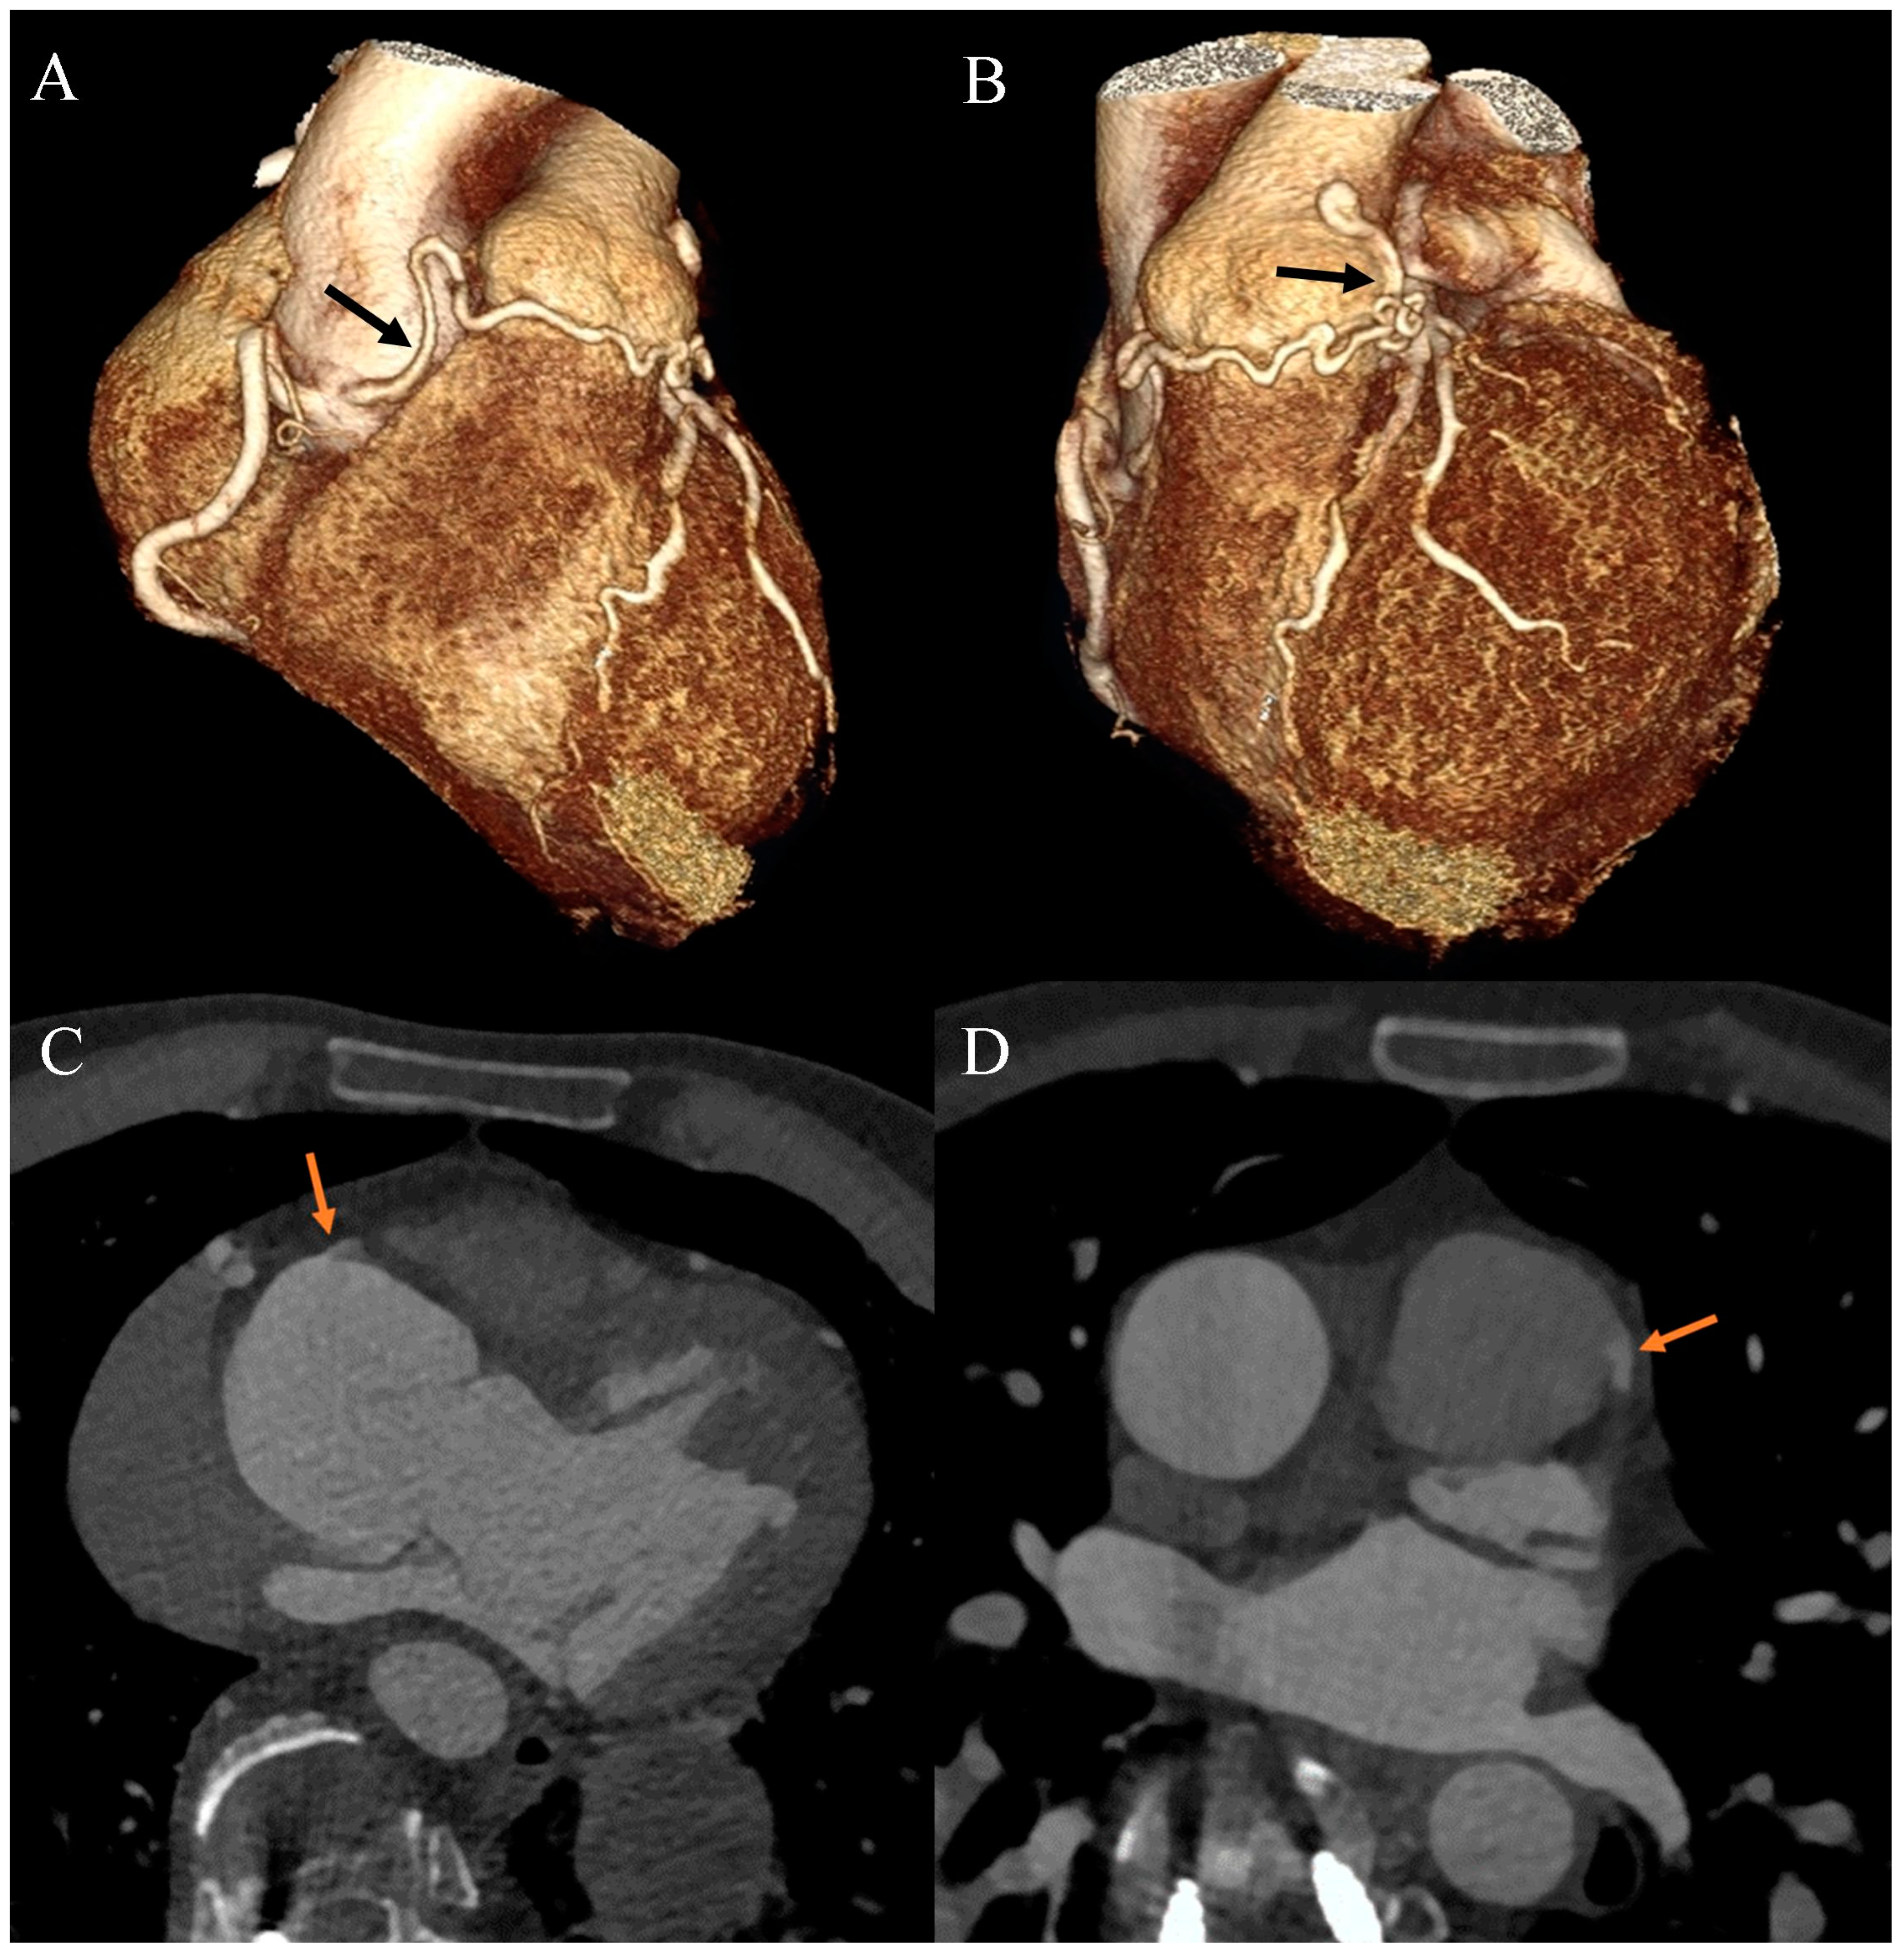

Figure 3.

Coronary artery computed tomography angiography. Coronary–pulmonary arterial fistula. (A) Volume-rendering technique reconstruction. Anterior-right view. The arrow indicates the proximal part of the fistula. (B) Volume-rendering technique reconstruction. Anterior-left view. The arrow indicates the distal part of the fistula. (C) Multiplanar reconstruction. Axial view. The arrow indicates the origin of the fistula from the right aortic bulb sinus. (D) Multiplanar reconstruction. Axial view. The arrow indicates the connection between the fistula and the main pulmonary artery.